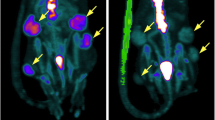

Consistent with average values, tumor uptake of 18F-FDG was significantly increased following RO injections at all timepoints as measured by dynamic PET over time within CT-identified ROIs (Fig. 3C, p = 0.029). While tumor uptake results suggest inefficient JV injection or enhanced extravasation following JV injection, equivalent small molecule probe distribution was observed over time in kidney, spleen, lung, and liver between JV and RO injection methods, suggesting efficient probe delivery within each method (Fig. 3D–G). Dynamic PET-CT images were examined for evidence of extravasation following JV injection, but none was observed at any timepoint. As can be seen in Fig. 4, high inter- and intratumor heterogeneity in probe uptake over time was observed, likely due to biological differences in tumor vascularization and metabolic activity of the tumors in each injection group. For example, while homogenous probe uptake was observed in the small tumor of the JV-injected mouse (Fig. 4A), regional differences in tumor uptake of 18F-FDG can be observed following RO injection due to the larger tumor size with highly metabolic outer edges and a hypometabolic necrotic core (Fig. 4A). Despite randomization, animals in the RO injection group presented with tumors with greater metabolic activity compared with tumors from animals in the JV-injected group. These differences are evident by the end of the 30 min scan, by which time 18F-FDG has fully distributed and limited variability in probe uptake can be observed between the two groups compared with the high variability in time-dependent uptake observed at earlier timepoints (Fig. 3C). These biological differences likely would have been minimized with greater sample size and resultant increased statistical power.

Representative dynamic PET overlayed on anatomical CT images following 18F-FDG injection. Sequential images at frames (minutes) 1, 10, 20, and 30 via either (A) JV or (B) RO injection methods are shown. Images demonstrate heterogeneous inter- and intratumoral uptake. Yellow dashed line on coronal view corresponds to slice shown in axial view. L liver, T tumor, B bladder.